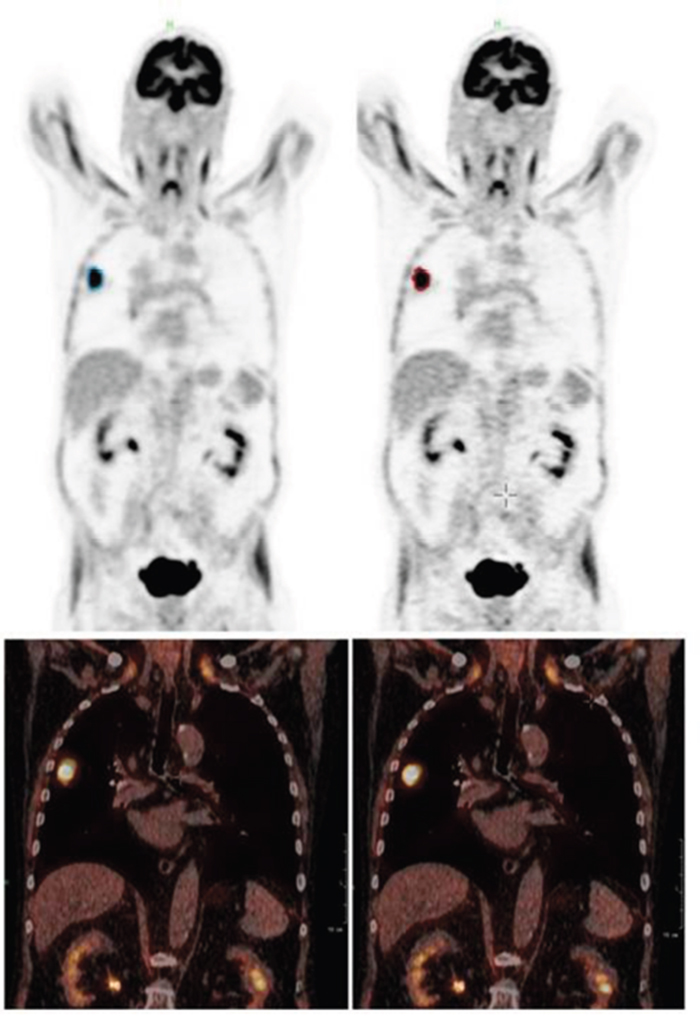

In patient data the detected lung lesion volume decreased between 5.6 and 15.6 % when using just the PSF in cranio-caudal direction and between 25.2 and 33.3 % when using the full 3D PSF for motion correction. Consequently, maximum uptake in the lesion showed an increase between 43.4 and 62.1 % and the mean uptake between 12.0 and 19.8 % when using the full 3D PSF. The details for each individual patient can be found in Table 1, an example can be seen in Figure 3.

Figure 3: Patient example (Patient 1): coronal PET (top) and fused PET/CT (bottom) of the uncorrected (left) and corrected (right) data set. Especially in the fused data set the tumor can be seen less smeared and better fitting to the CT image.